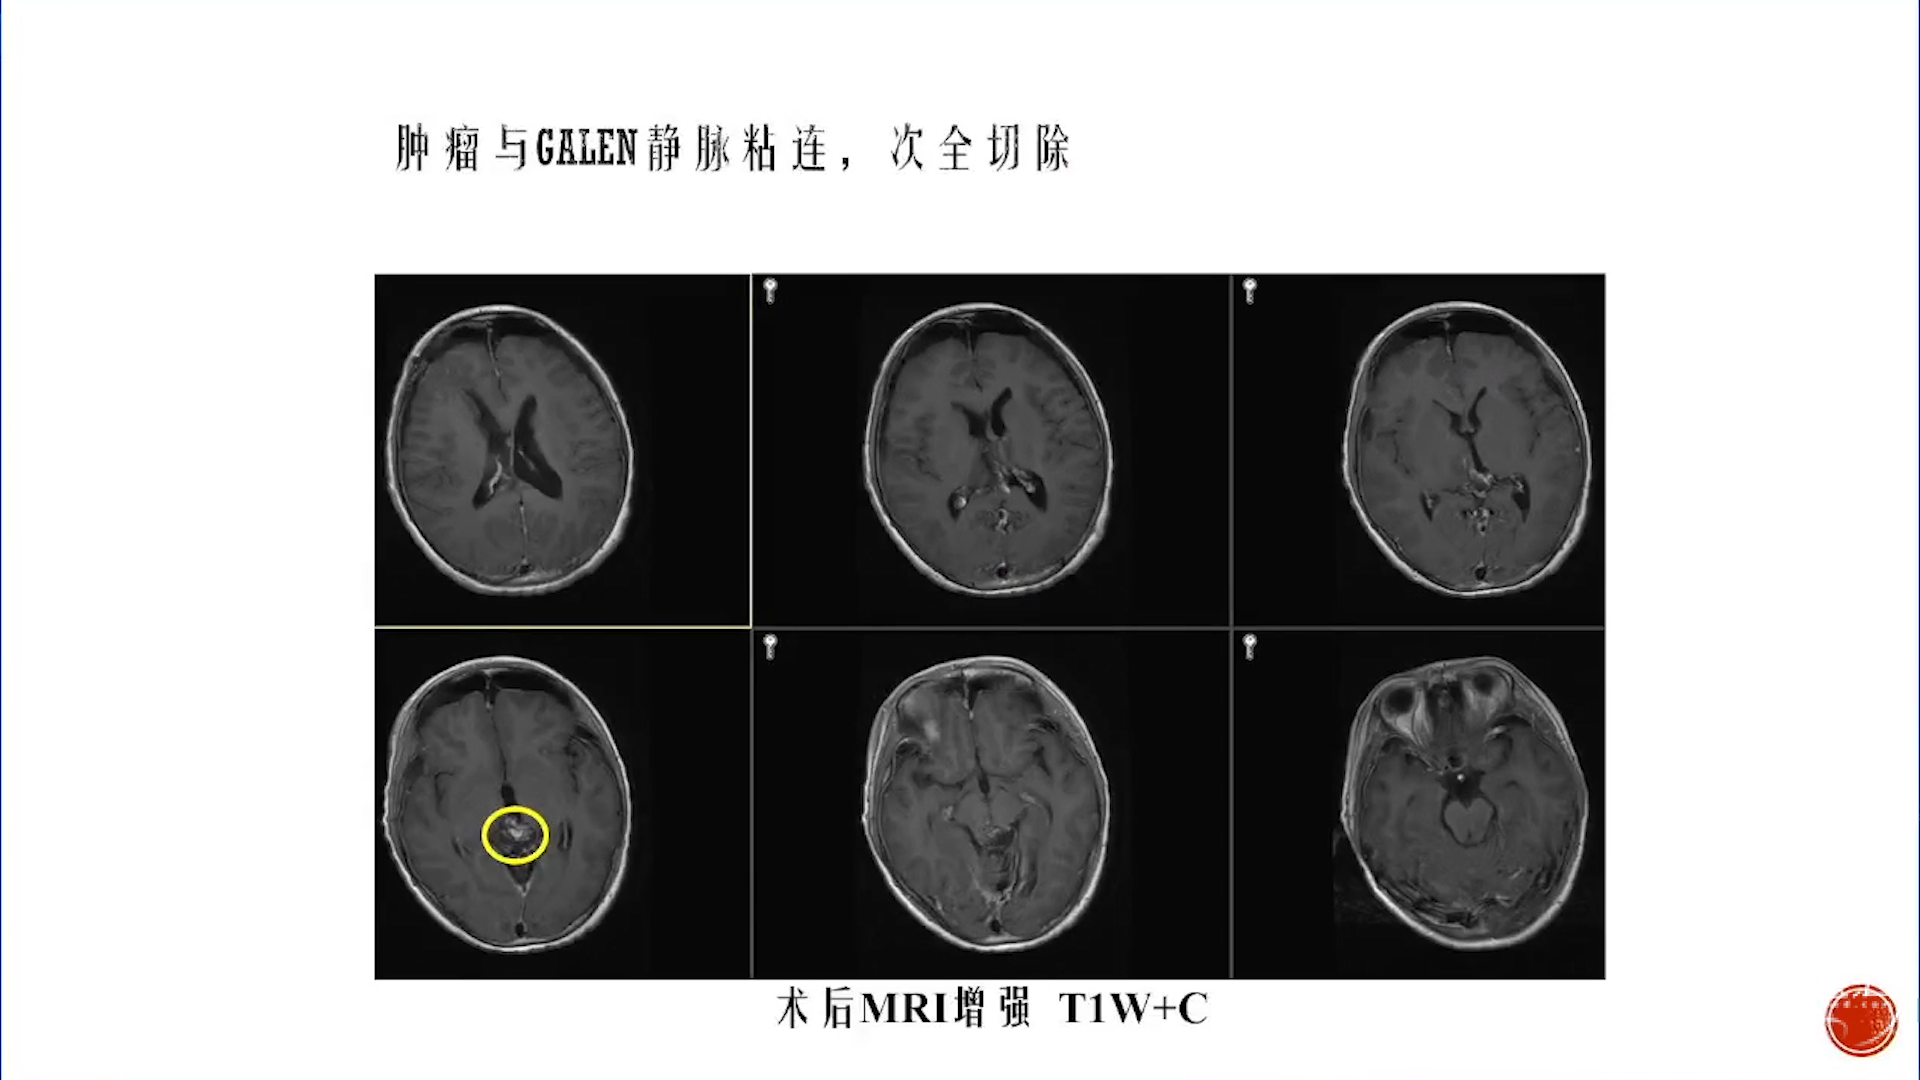

小脑星形细胞肿瘤